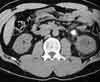

The noncontrast abdominal CT scan is shown here.

The CT scan shows a renal stone and mild hydronephrosis. In a patient with acute-onset right flank pain that radiates to the groin, no localizing signs, and microscopic hematuria, these findings strongly suggest nephrolithiasis, C.